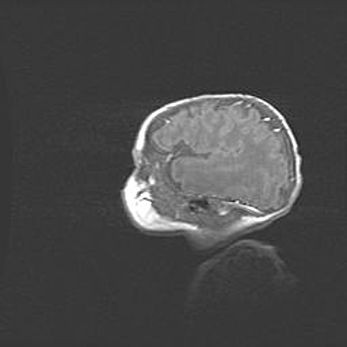

Мальформация Денди-Уокера. Киста задней черепной ямки.

Агенезия мозолистого тела.

Возраст: 2,5 месяца

Вес: 2420 г

Пол: женский

Окружность головы: 37 см

Срок гестации: 32 недели

Мальформация Денди—Уокера — редкий вид патологии ЦНС, представляющий собой врожденный порок развития каудального отдела ствола и червя мозжечка, ведущий к неполному раскрытию срединной (Мажанди) и латеральных (Лушка) апертур IV желудочка мозга. Для этогно синдрома характерна триада симптомов: гипотрофия червя мозжечка и/или полушарий мозжечка, кисты задней черепной ямки, гидроцефалия различной степени. В 70% случаев порок сочетается и с другими аномалиями головного мозга, в частности с агенезией мозолистого тела.